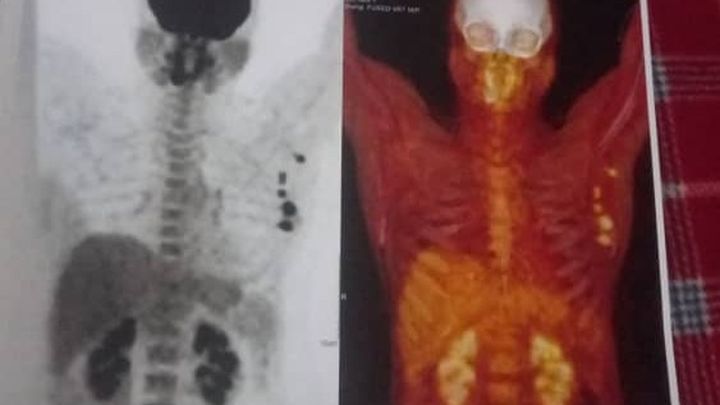

Recently, Maria was diagnosed with Stage 3 Breast Cancer. The words no one ever wants to hear. Her treatment is aggressive and urgent: she requires a mastectomy (surgical removal of her breast) followed by intensive chemotherapy. The physical and emotional toll of this alone is unimaginable.